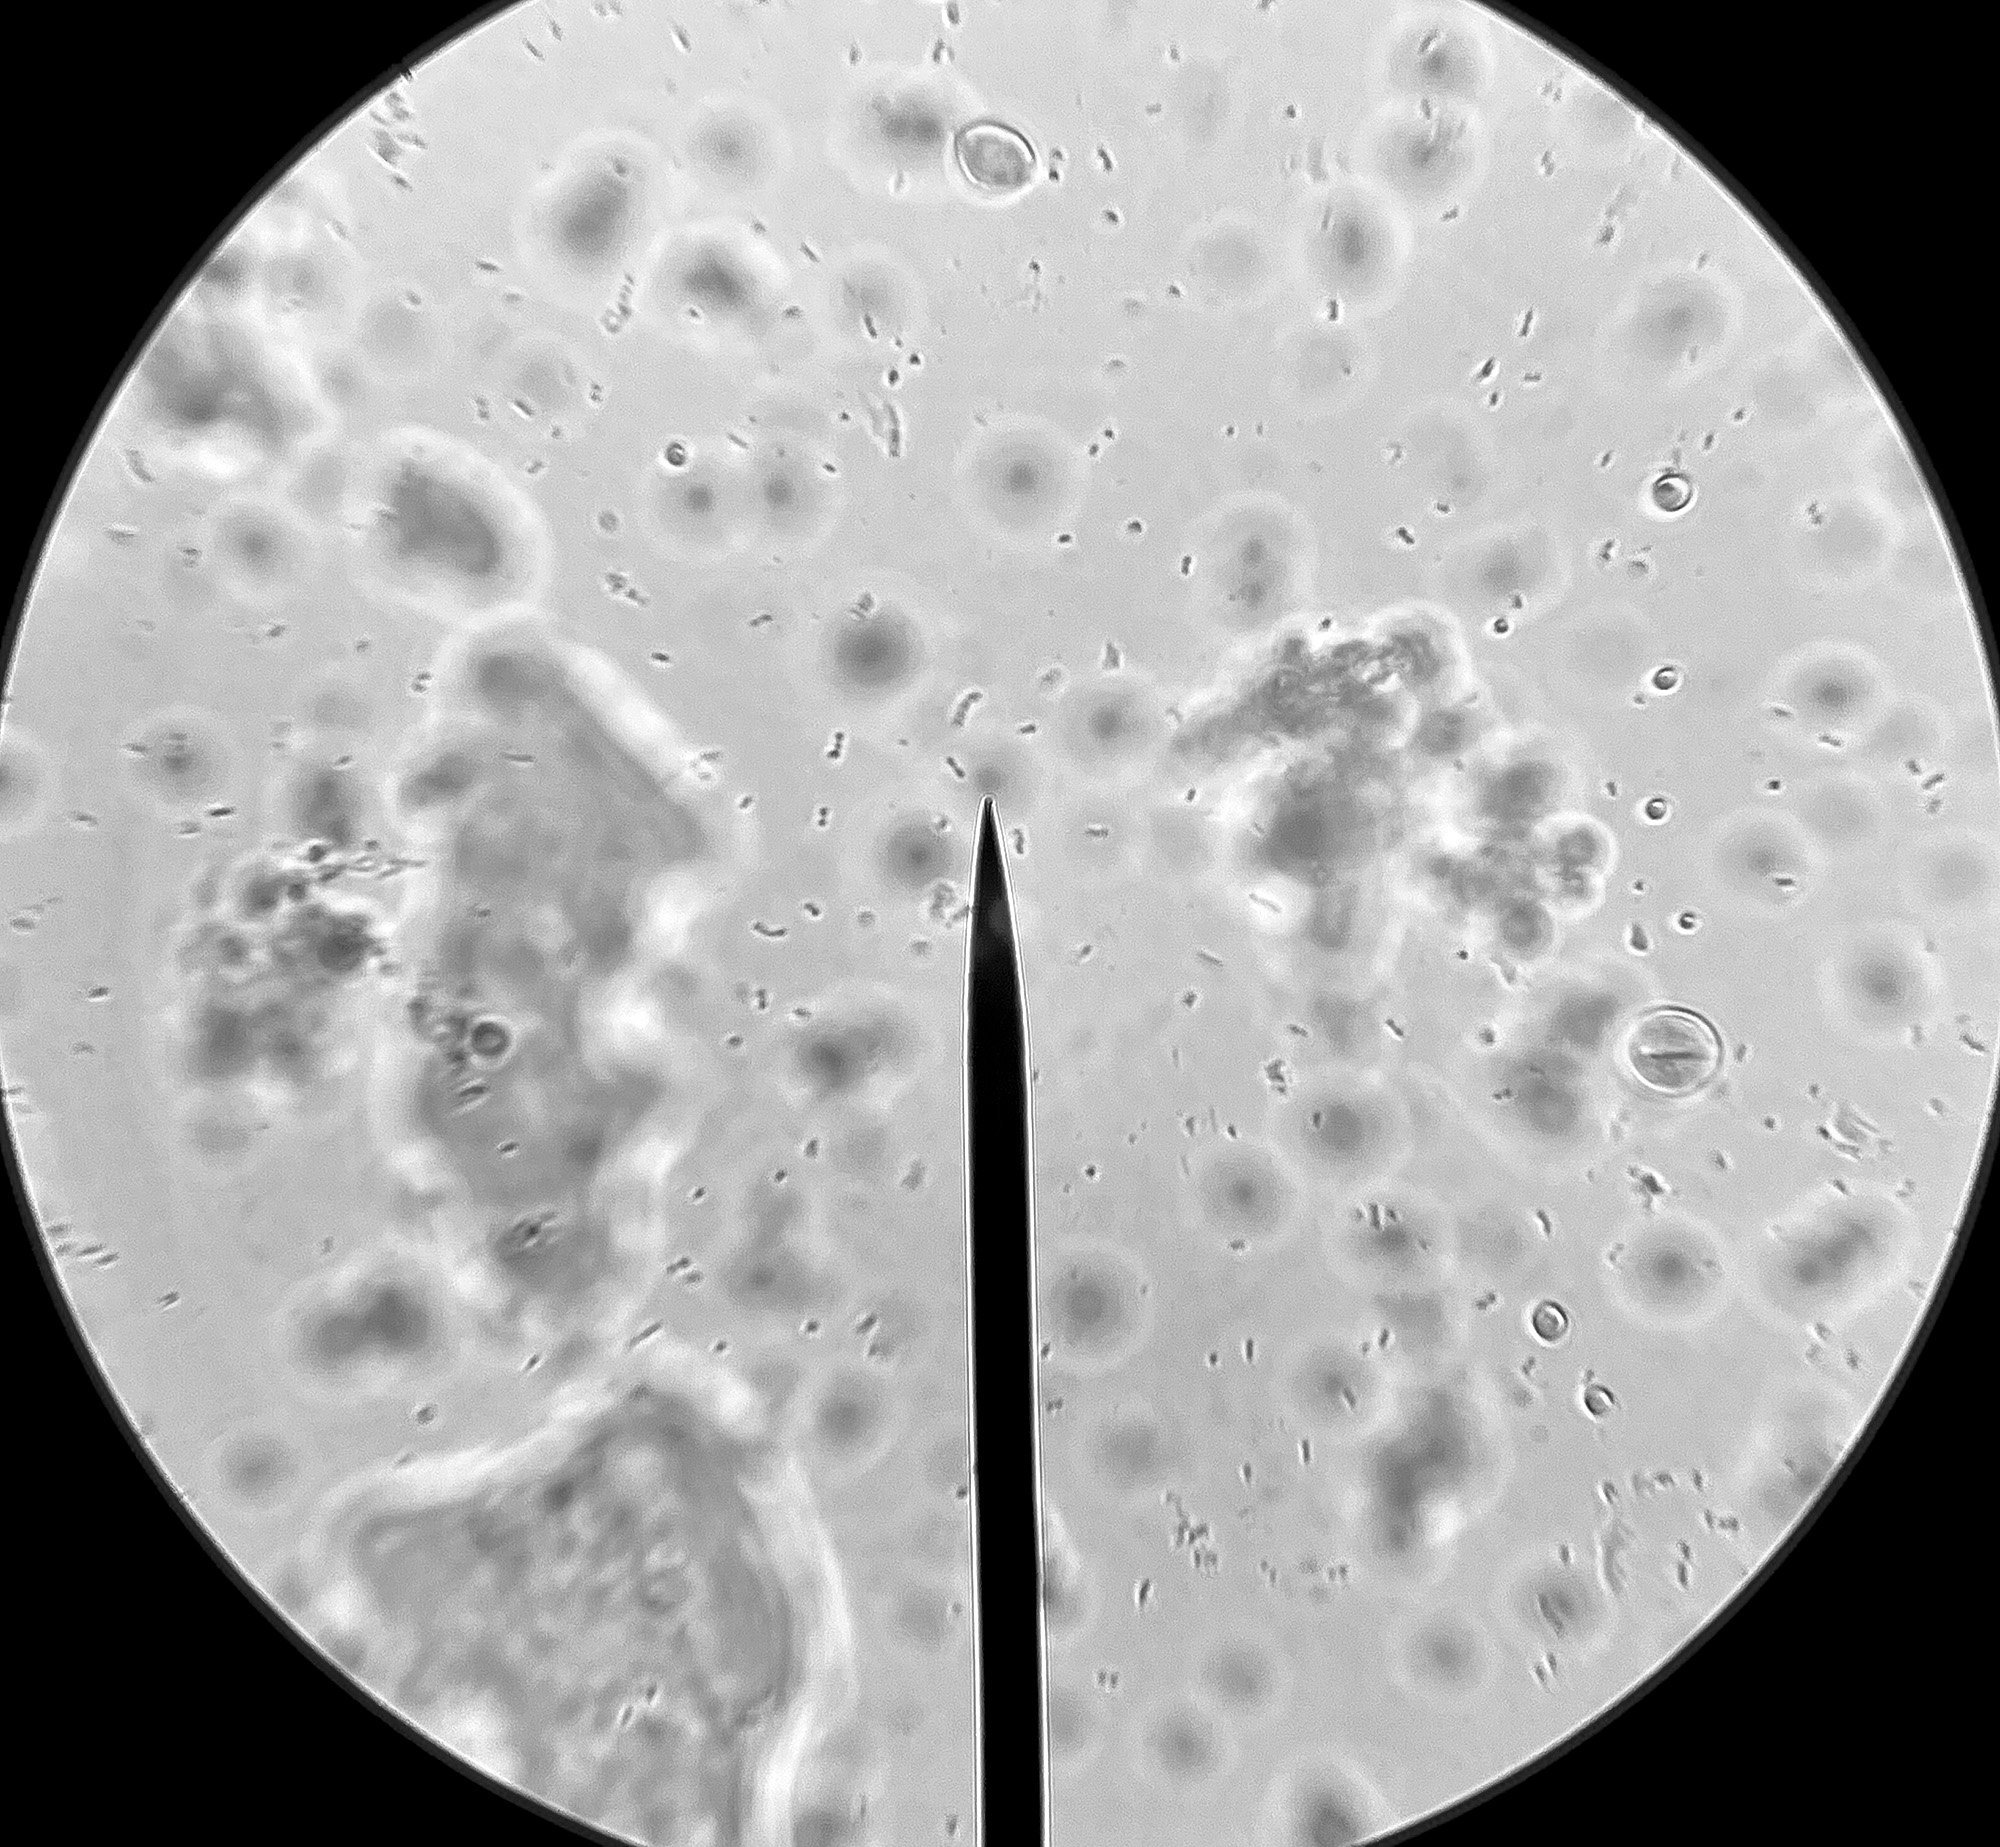

Какви видове бактерии са открити в домашно приготвените продукти?

Защо някои хора смятат, че в киселото мляко не присъства Lactobacillus reuteri след 36 часа?